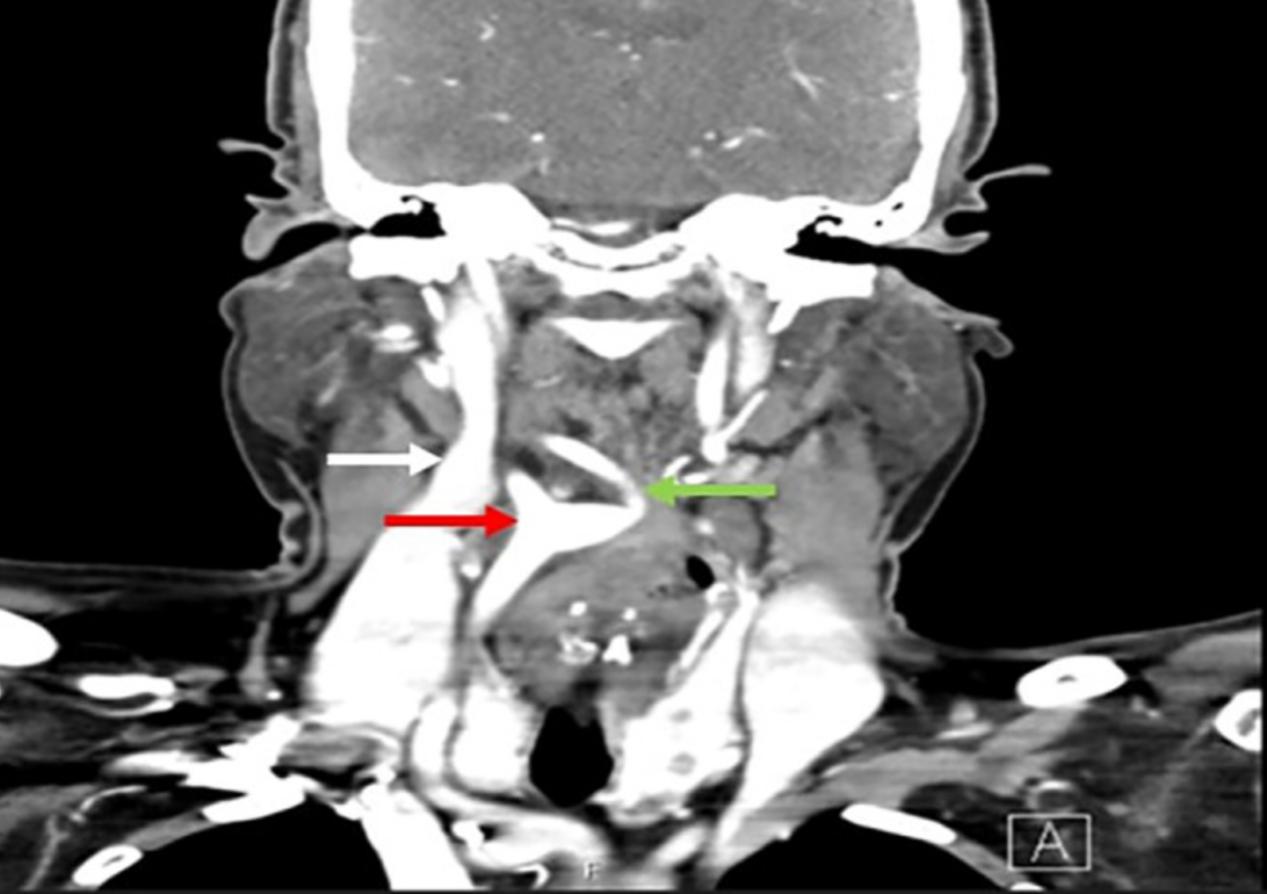

颈部CT扫描证实右颈动脉分叉居中,内支(图2)位于咽后脂肪间隙内,并向前和向下压迫右侧杓状软骨及梨状窝,导致声门平面异常(图3和4)。根据患者5年前的CT检查,排除了动脉瘤的假设,因为两次颈部图像无明显变化。考虑症状较为罕见,且手术并发症发生率较高,手术医生建议保守观察。

图2 颈部CT扫描,冠状位:颈动脉分叉居中(红色箭头),右颈内动脉(绿色箭头),右侧颈内静脉(白色箭头)